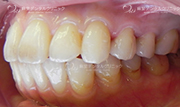

セラミックインレー

当院で扱っているセラミックインレーにはe.max(イーマックス)とジルコニアがあります。

ジルコニアインレーの方が強度がありますが、e.maxインレーの方が色が合わせやすく自然な仕上がりになる事が多いです。

ジルコニアインレーはCAD/CAMという技術により製作された物を使用し、e.max(イーマックス)はプレスいう技法で製作された物を扱っています。